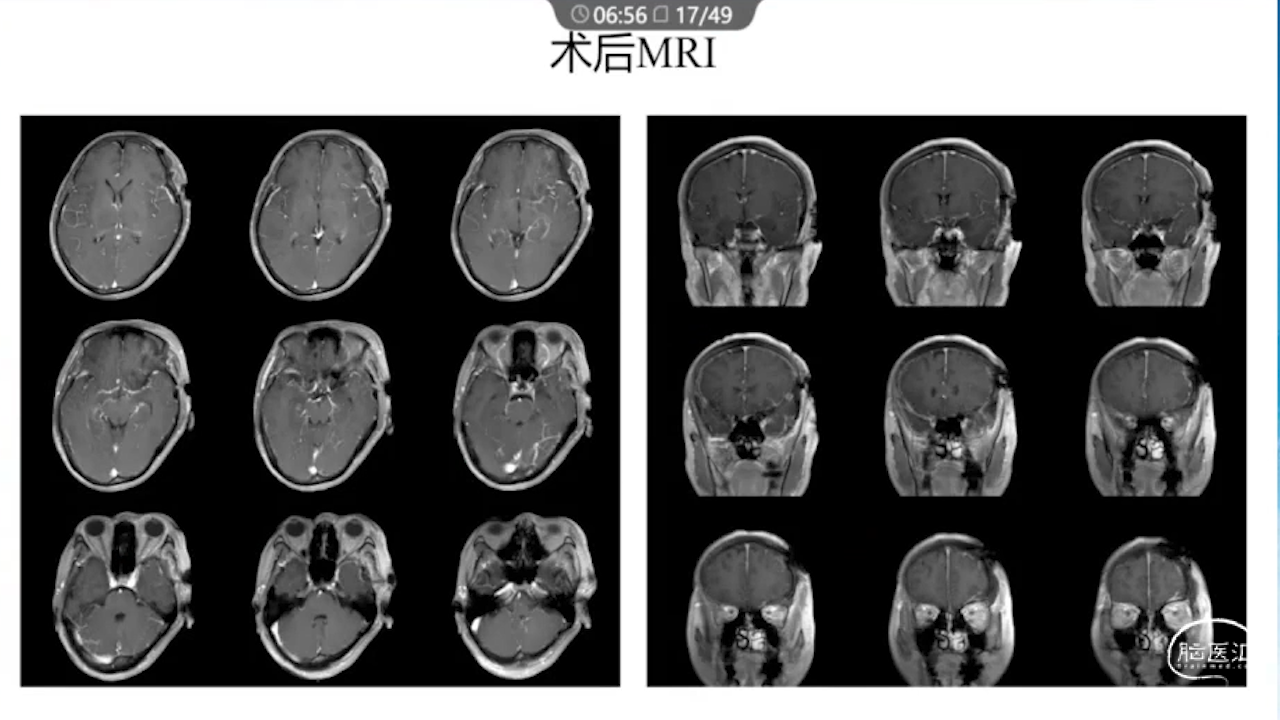

1、术前需要完善的影像学检查、多模态融合及神经导航以进行精确的肿瘤及静脉血管定位。

8、术后积极进行脱水治疗:如果术后脱水不及时,将可能发生严重的脑水肿,导致功能区脑组织受压、静脉回流障碍等一系列的严重反应。